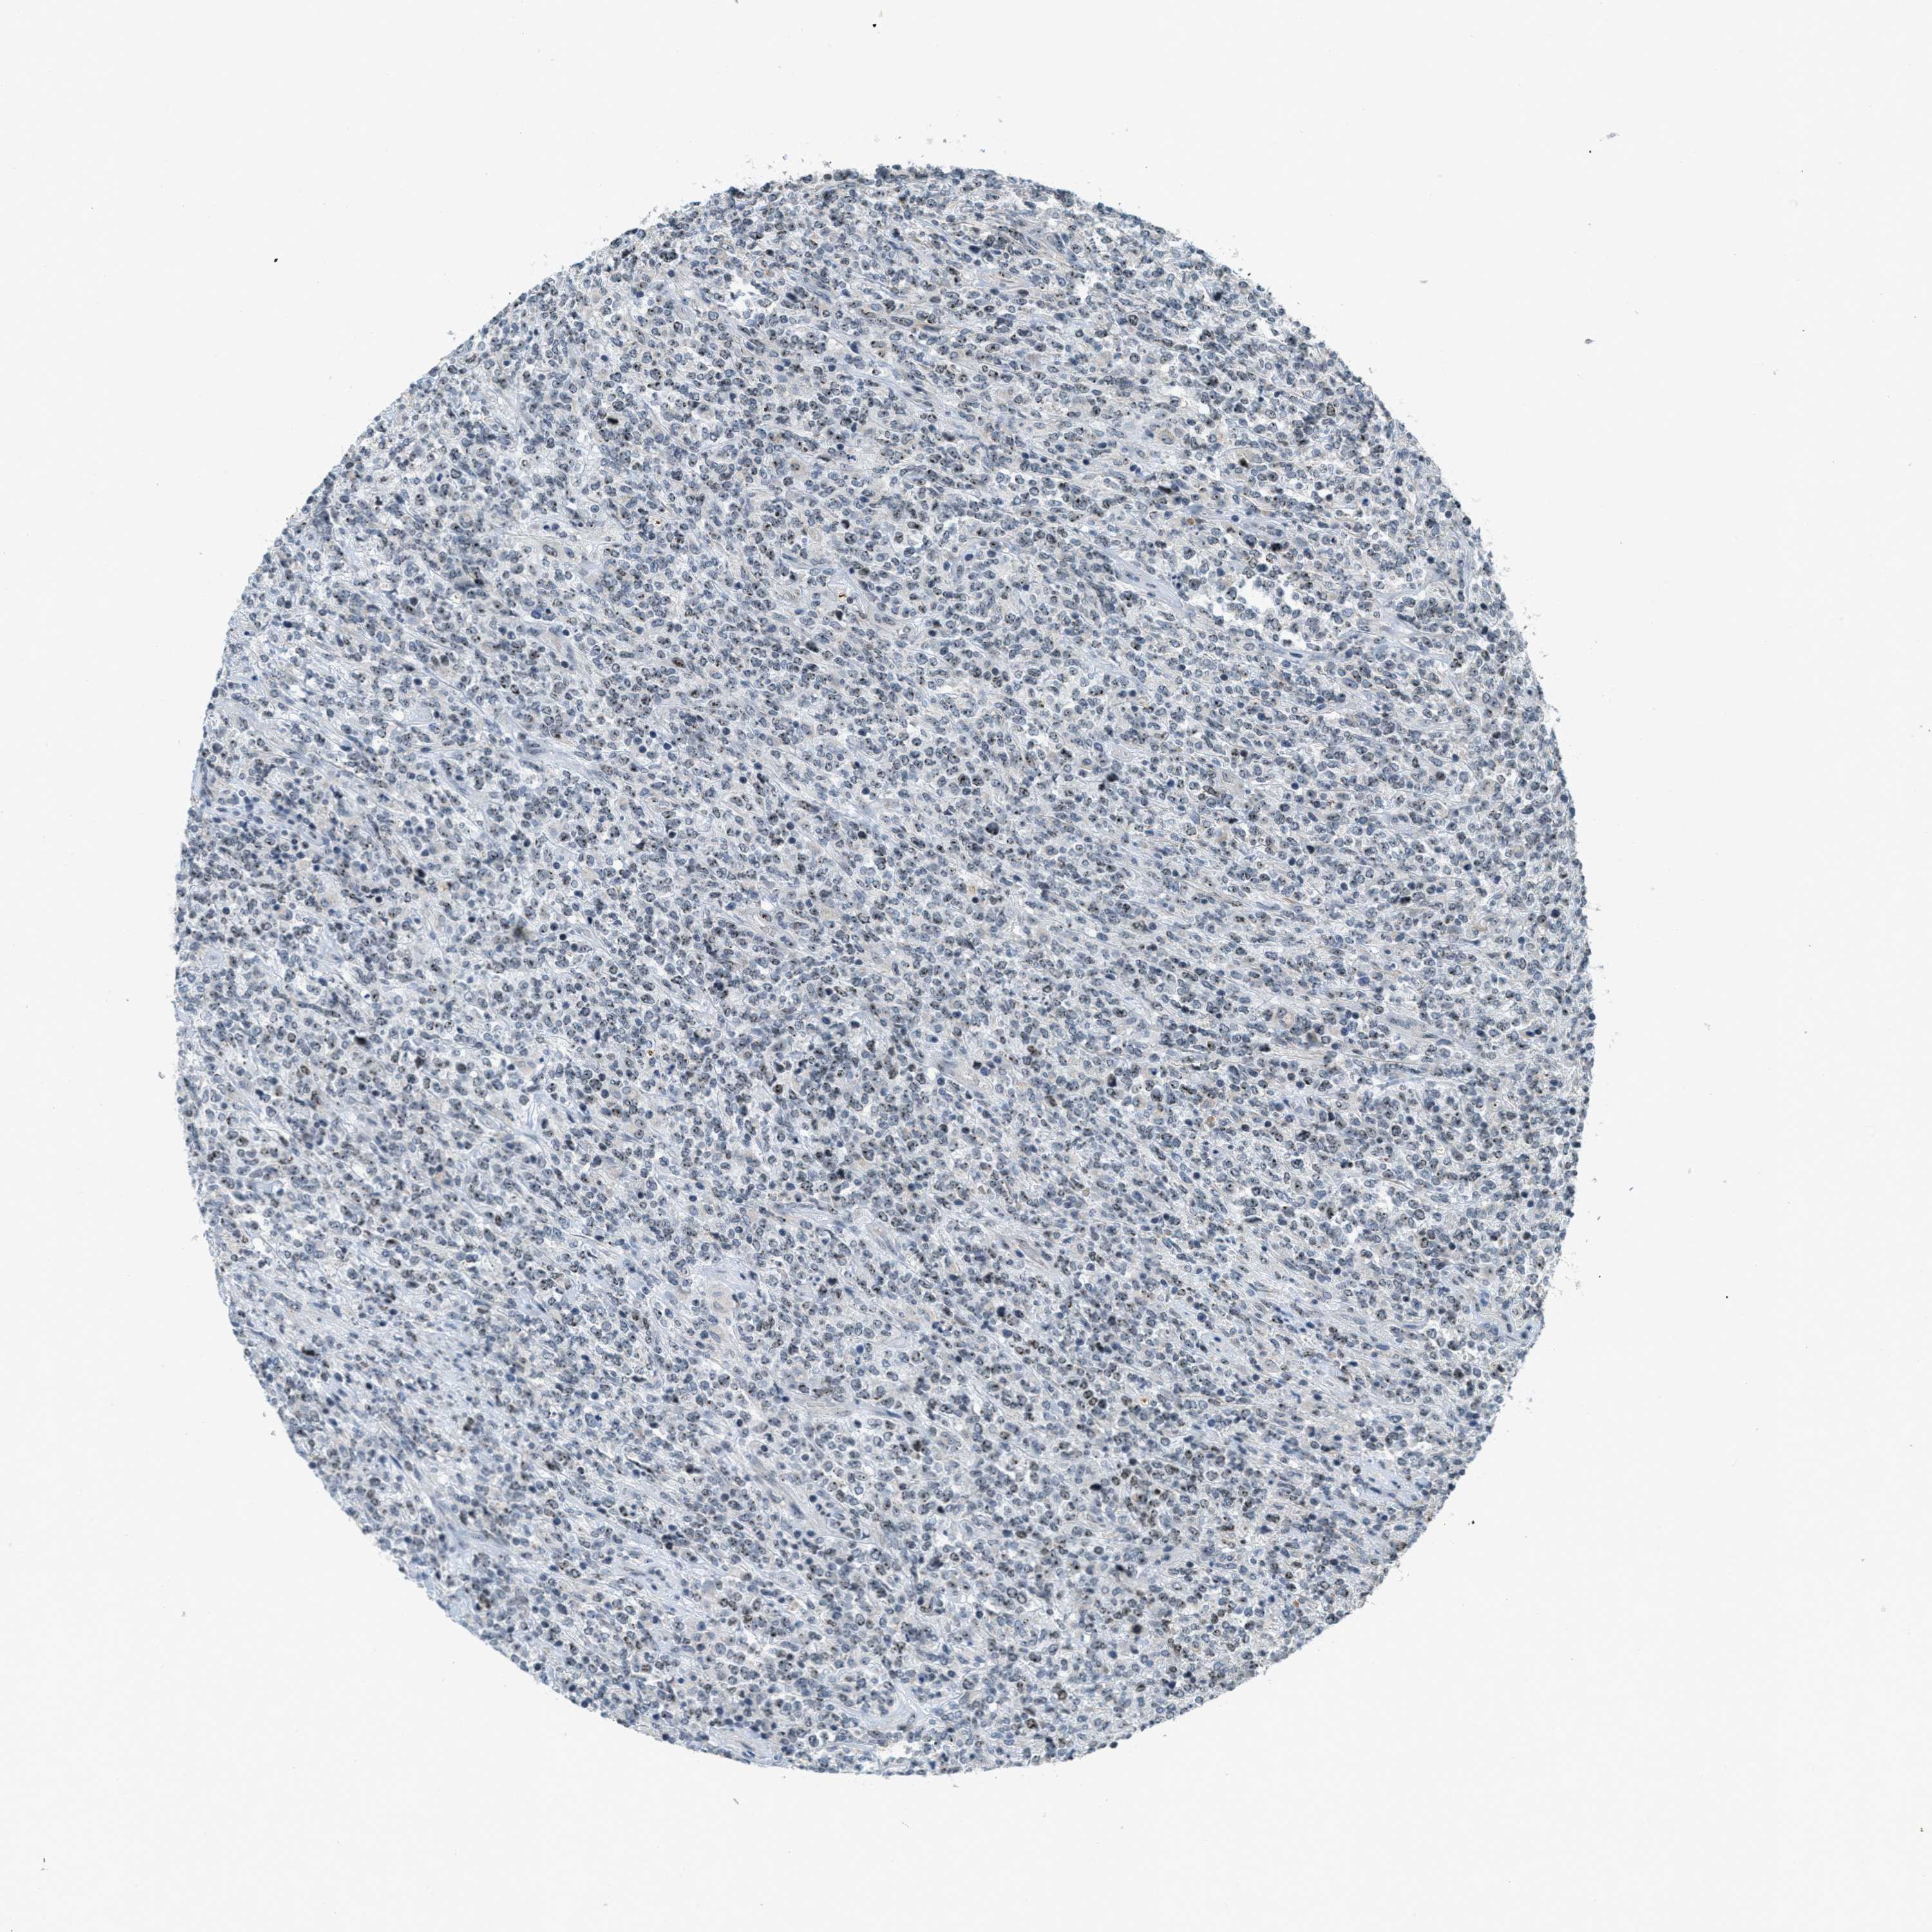

LYMPHOMA - Protein expressioni

A mouse-over function shows sample information and annotation data. Click on an image to view it in a full screen mode. Samples can be filtered based on level of antibody staining by selecting one or several of the following categories: high, medium, low and not detected. The assay and annotation is described here.

Antibody stainingi

Antibody staining in the annotated cell types in the current human tissue is reported as not detected, low, medium, or high, based on conventional immunohistochemistry profiling in selected tissues. This score is based on the combination of the staining intensity and fraction of stained cells.

Each image is clickable and will lead to virtual microscopy that enables deeper exploration of all samples and also displays staining intensity scores, fraction scores and subcellular localization as well as patient and tissue information for each sample.

Antibody HPA014855

Hodgkin's disease, NOS

Malignant lymphoma, non-Hodgkin's type, High grade

Malignant lymphoma, non-Hodgkin's type, Low grade